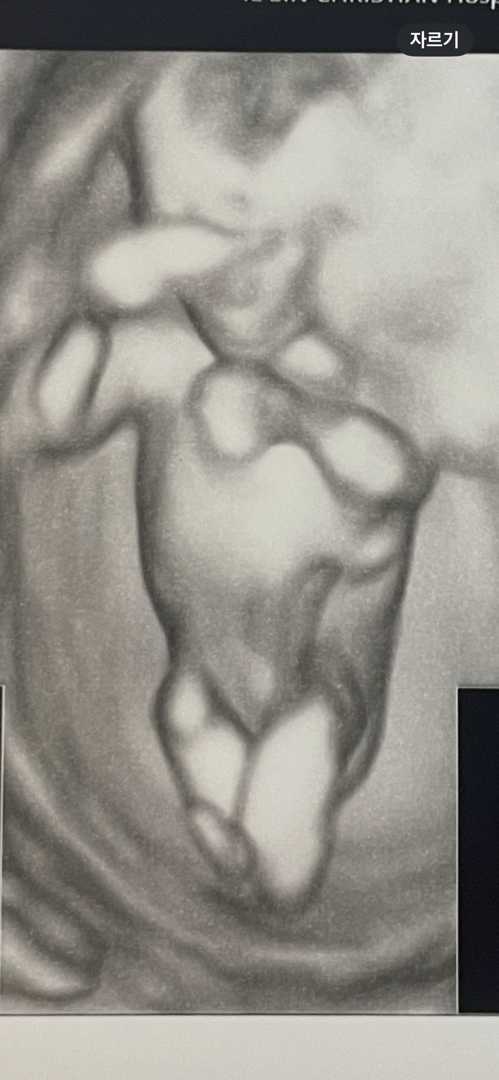

12주 5일차 입체초음파

다리를 꼬고 있어서 보여주질 않았는데 가운데가 넘 매끈한게 딸같지 않나요? 고추가 있었으면 불편해서 쩍벌하지 않았을까 싶고 ㅋㅋㅋ애미는 애타네요 고추인지 아닌지 ㅋㅋㅋㅋㅋㅋㅋㅋㅋ